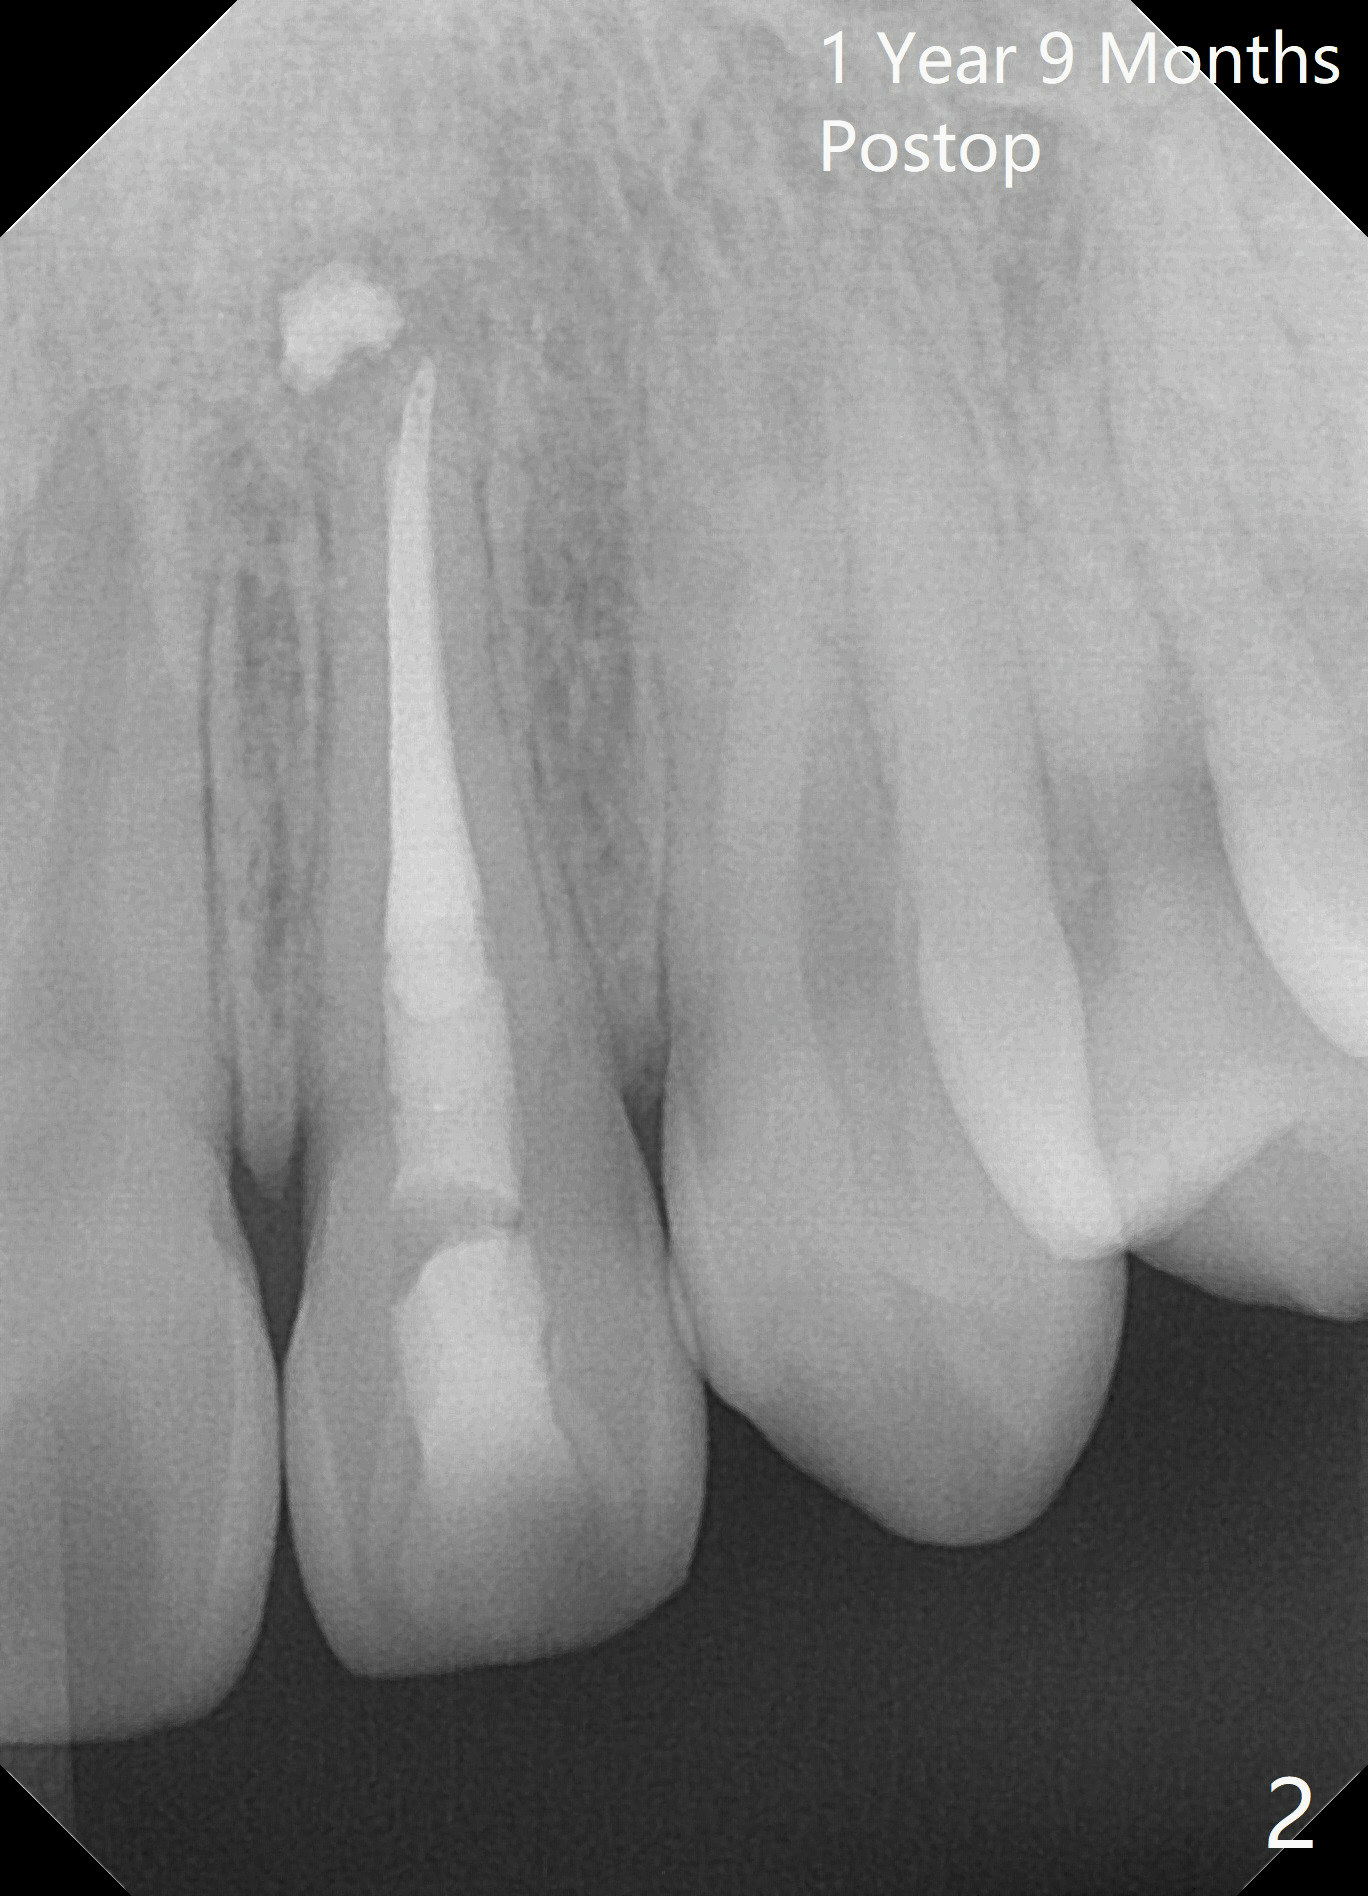

A 18-year-old man develops acute apical periodontitis at #10 several years after phase I and II orthodontic treatment. Fig.1 is taken immediately post RCT with #70 master gutta percha (GP) and 2 medium and 1 fine fine accessory GP. Periapical radiolucency reduces 1 year 9 months postop (Fig.2). The patient reports occasional tingling 2 years 3 months postop (Fig.3).